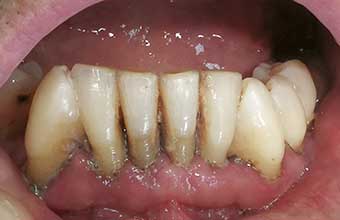

O primeiro passo é a raspagem e o alisamento radicular. O dentista faz uma limpeza profunda para remover todo o tártaro e a placa bacteriana acumulada nas raízes dos dentes.

- Limpeza Profunda (Raspagem e Alisamento Radicular): O dentista fará uma limpeza detalhada para remover todo o tártaro e placa bacteriana que se acumularam abaixo da linha da gengiva. Isso pode ser feito com instrumentos manuais (curetas) ou ultrassom. O objetivo é deixar as raízes dos dentes bem lisas, dificultando a volta das bactérias.

A base do tratamento para a periodontite juvenil é a remoção mecânica do biofilme e do tártaro. Sem essa limpeza profunda, nenhum outro tratamento tem chance de sucesso. É como tentar pintar uma parede suja: a pintura não vai aderir direito. O dentista usa instrumentos específicos para chegar onde a escova e o fio dental não alcançam, limpando as bolsas periodontais.